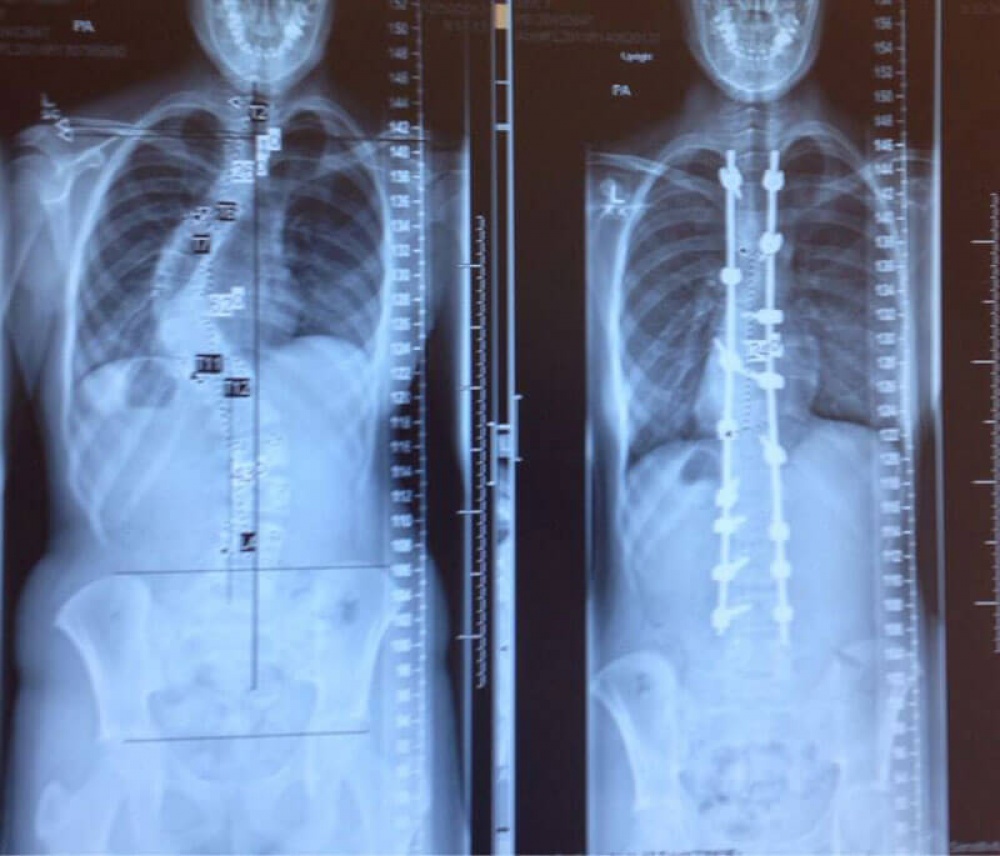

Միևնույն մարդու ողնաշարը` սկոլիոզի բուժումից առաջ և հետո